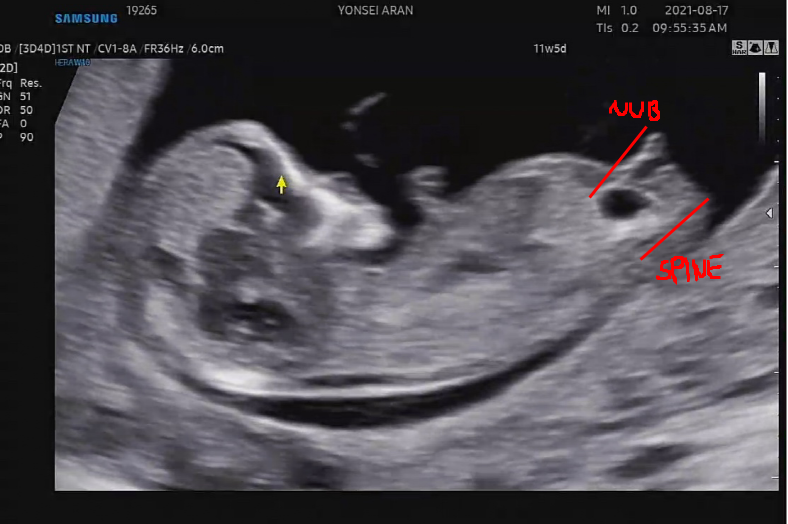

각도법

11주 5일 초음파를 보러갔다.

이 때 받은 초음파 영상을 분석해서 아들이 아닐까 추측하게 되었다.

처음에는 각도법도 난황법이나 떠도는 각종 성별을 알아보는 법처럼 부정확한건줄 알았는데

나름 신뢰도가 높은 것 같았다.

외성기(NUB)와 척추뼈(SPINE)의 각도를 보는건데

각도가 수평이면 여아고

30도 이상이면 남아라는데..

우리 포도는 아무리봐도 수평은 아닌 것 같았다.